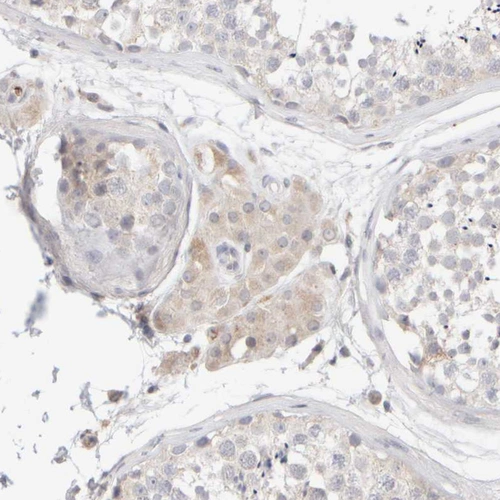

Immunohistochemical staining of human liver shows strong cytoplasmic positivity in hepatocytes.